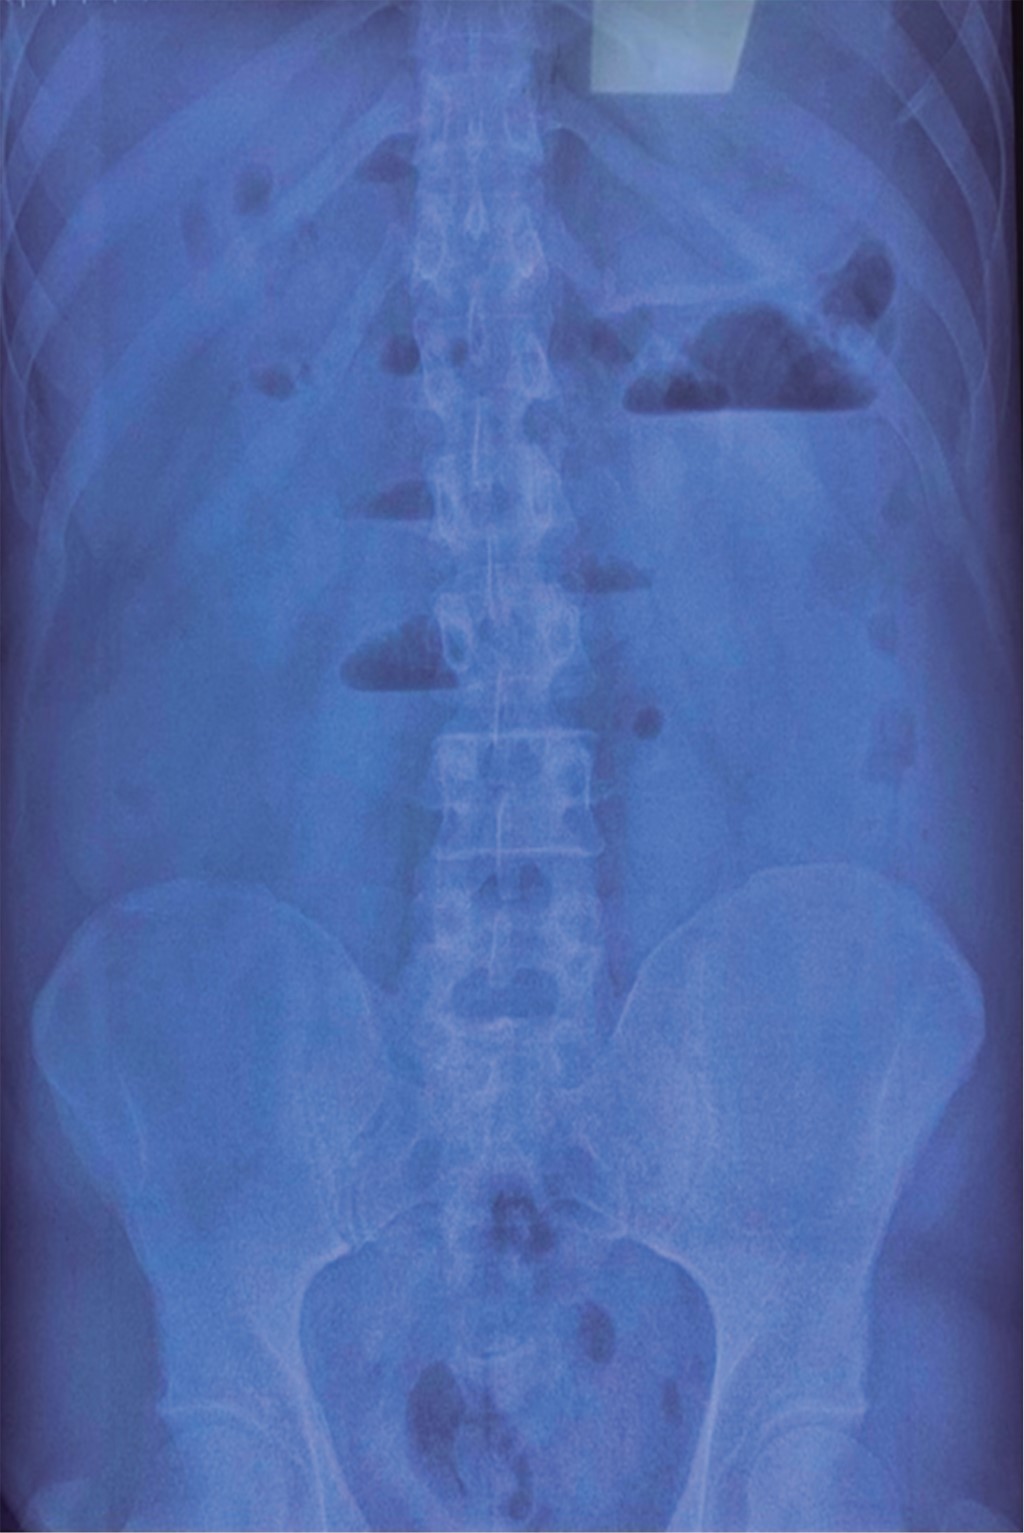

On standing and decubitus abdominal simple radiographs (Figure 1) a coin stack image was evidenced, as well as distension of the small bowel loops, with the absence of gas in the distal intestine.

The imaging studies began with abdominal radiographs in which Rigler's triad was expected to be evidenced: ectopic gallstone, pneumobilia, and distension of intestinal loops; the diagnosis is considered when two of these are present, and we speak of Rigler's tetrad when the change of position of the stone concerning the previous radiograph is documented.1,2 In our patient, it was impossible to find these findings since the simple abdominal X-rays only showed a hydro-aerial level in the right hemiabdomen, distension of intestinal loops, and absence of air in the distal intestine.

Chang and colleagues, in 2018, reported that Rigler's triad on radiographs is present in 14 to 53% of cases, whose sensitivity is 40 to 70%, as well as the visualization of gallstones in 10 to 20% of cases in those containing calcium to be radio opaque.2,6 This was also according to what was found in our patient. For that reason, a cholesterol stone was thought to be present, and since there was no apparent cause of the obstruction, a contrasted abdominal tomography scan was requested, which is currently considered the study of choice for diagnosis since it is possible to visualize Rigler's triad in up to 80% of cases with an approximately 90% sensitivity.1,6

Figure 2